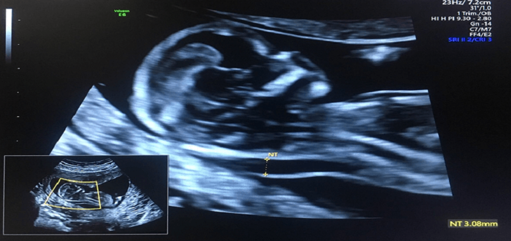

Siêu âm độ mờ da gáy được thực hiện từ tuần thứ 11 - 13 của thai kỳ được xem là một phần của xét nghiệm sàng lọc hội chứng Down trước sinh. Vì thế, kết quả siêu âm trong giai đoạn này luôn được thai phụ quan tâm. Vậy khi thai phụ siêu âm có kết quả đo độ mờ da gáy bất thường cần làm gì?